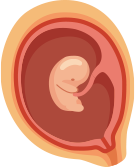

임신 기간 동안 산모와 태아의 상태를 확인하며 주수에 따라 필요한 검사와 관리가 이루어질 수 있습니다. 산전관리에서는 임신 기간별 영양 관리와 주수별 검사, 특수 초음파 검사를 통해 태아의 성장 상태를 확인합니다.

임신 기간 동안 태아의 성장과 건강 상태를 확인하기 위해 정밀 초음파 검사가 진행될 수 있습니다.